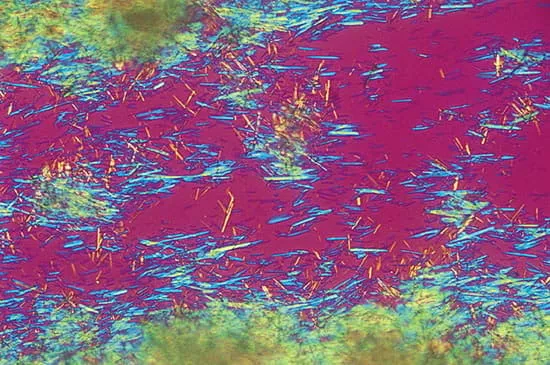

Рис 11. Кристаллы моноурата натрия в поляризованном свете. На этом снимке, полученном с помощью поляризационного микроскопа с применением красного компенсационного фильтра, видны характерные двоякопреломляющие игольчатые кристаллы уратов из аспирата тофуса. Кристаллы с отрицательным двойным лучепреломлением выглядят желтыми, если они лежат параллельно оптической оси компенсатора, и синими, если они перпендикулярны ей [9].

Интерпретация:

- Выявление игловидных кристаллов с отрицательным двойным лучепреломлением характерно для кристаллов моноурата натрия при подагре.

Мелкие ромбовидные кристаллы с положительным двойным лучепреломлением - кристаллы пирофосфата кальция, отмечаются при пирофосфатной артропатии (псевдоподагре).